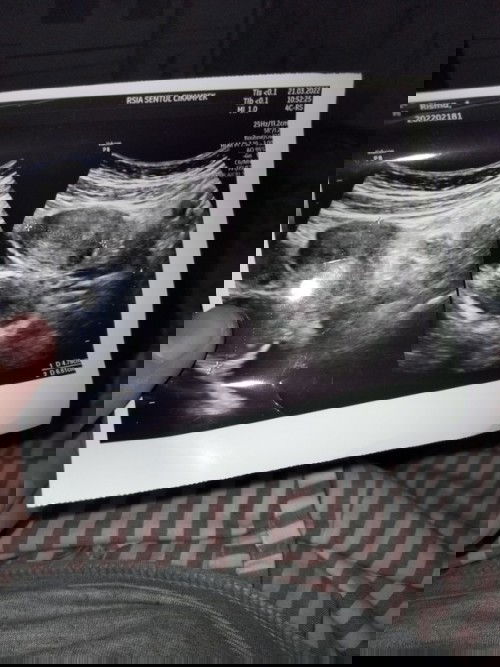

Hamil 5 week, saat USG masih kosong

Mom, ada yg pernah ngalamin ga, hamil 5 week tpi pas usg ga keliatan apa², aku sampe dokter nya nyuruh buat tespek ulang dan dia agak heraan hasil nya positif tapi ko rahim nya ga ada apa², kantong nya pun blm nampak.. trus juga skrg aku keluar bercak darah warna coklat, ga sakit sih tapi worry bgt, 2 minggu lagi aku check lagi buat memastikan apakah janin ku berkembang atau ngga, doain smoga janin nya ada ya mom🥺 ini kehamilan kedua ku setelah 5 bulan lalu keguguran😔 #seriusnanya #bantusharing #ingintahu #pleasehelp #firstbaby #firstmom